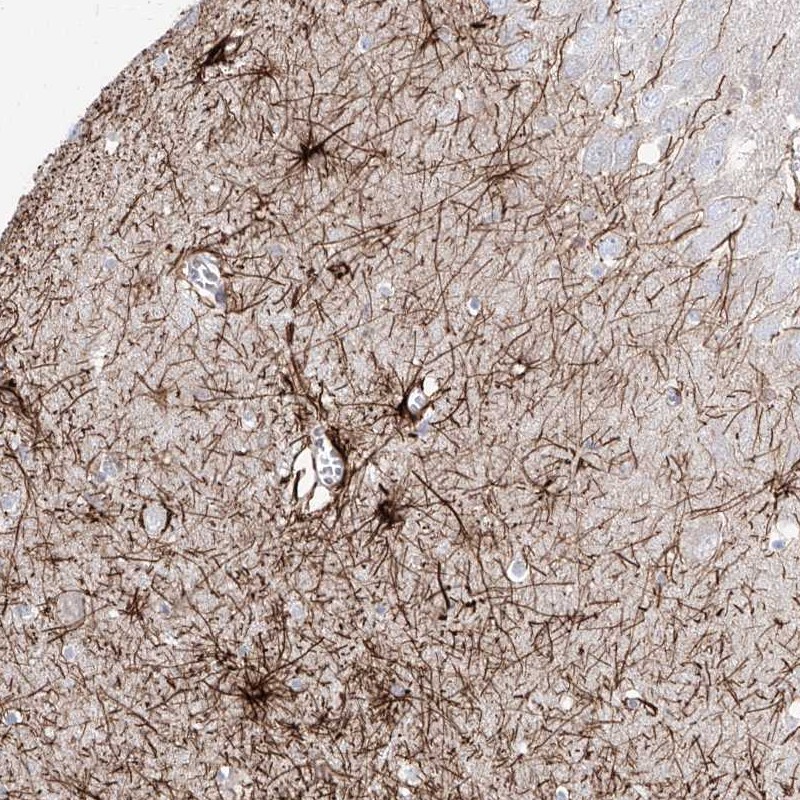

Immunohistochemical staining of human hippocampus shows strong cytoplasmic positivity in astrocytes.